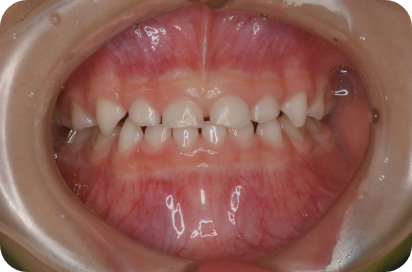

Tさん

Before

After

- 形態:狭いV型の上顎を丸くて広いU型に改善、歯ならび、咬み合わせの改善

- 機能:咀嚼嚥下トレーニング、口腔周囲筋トレーニング、姿勢改善